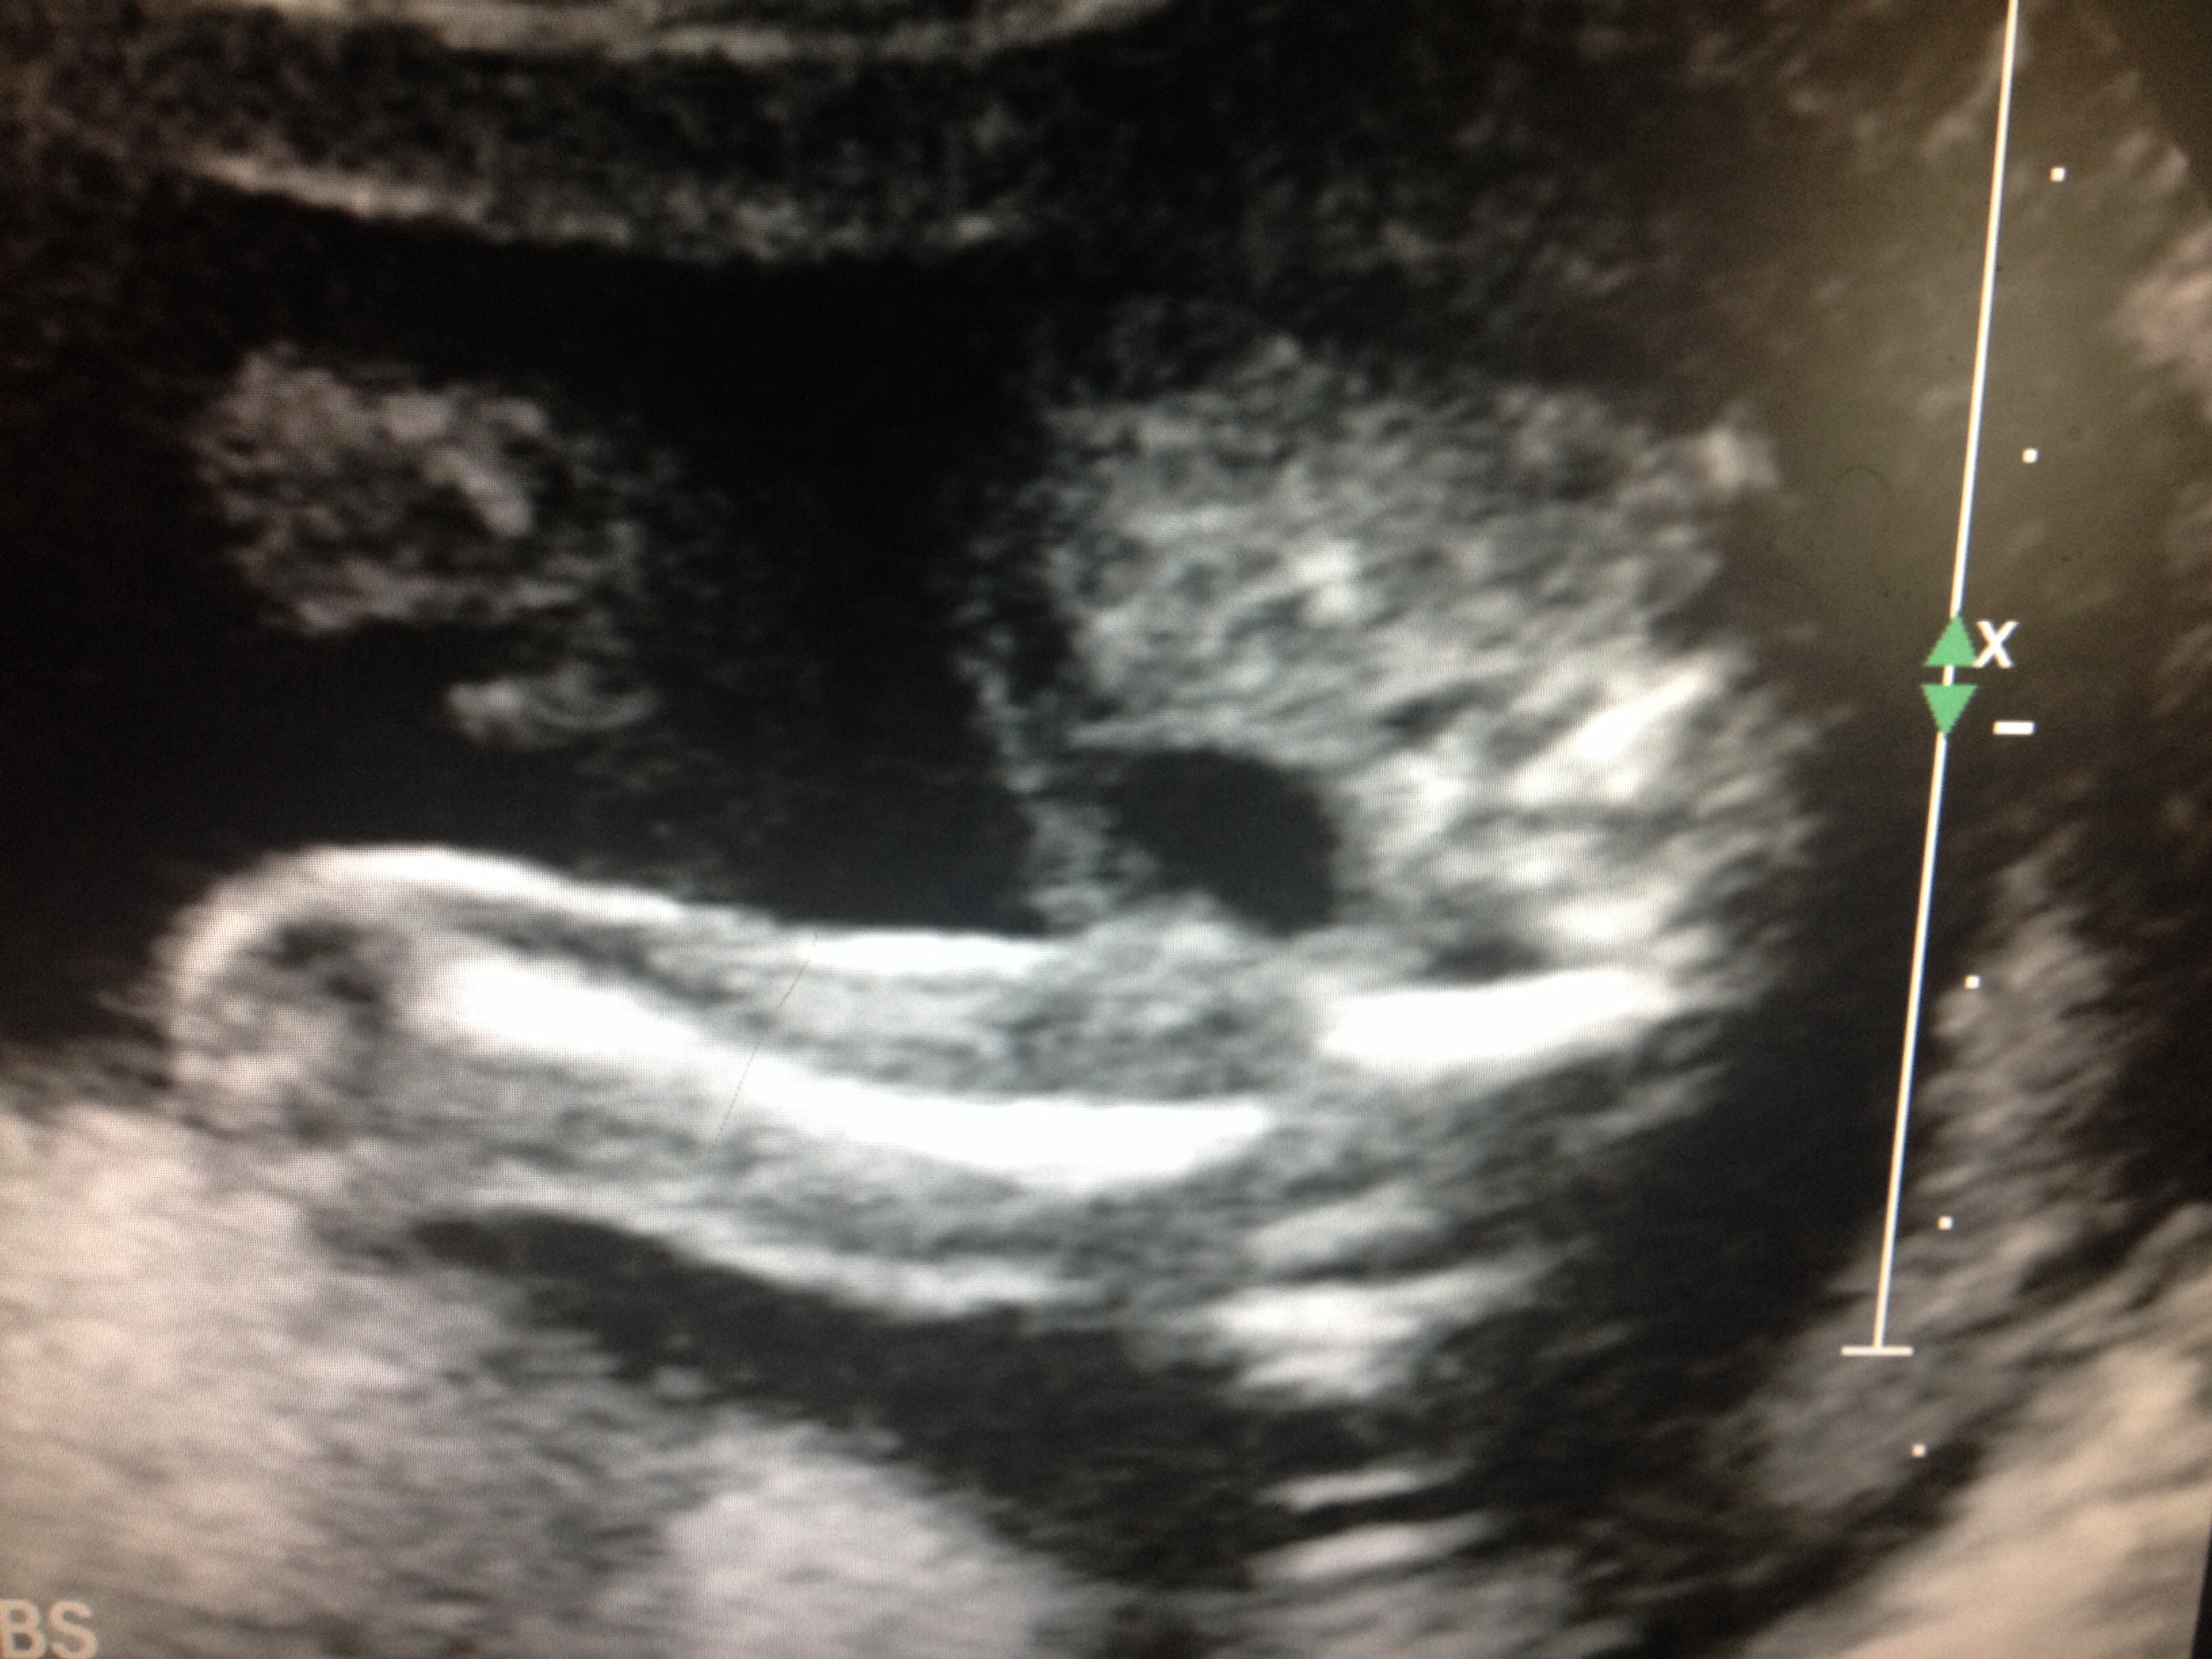

Attachment 15059Hubby doesn't want to know so we it didnt find out. I want to Know!! WhAt do you thinkAttachment 15048? Boy or girl?

The legs are really close together, so it's kind of a toss up. But I'd be inclined to lean boy because there is something going on between there. I had a similar shot with my girl, but there was only lines way far back. So I guess I'd lean a little bit boy. However, it's just a guess.

Hate these dubious one....I have to agree I would lean more boy then girl as I don't see any lines at all....my baby had lots of lines but sticking too far out even then looked dubious but turned out to be boy.....

Mmm Im actually going to go with Girl!

I thought girl, my boy scan was VERY obvious! x

I don't think it's clear enough to tell. My first thought was girl, but I'm really not sure.

My first thought was girl as well but I don't see 3 lines. Also sometimes boy bits can be tucked up. Even though the legs are closed on the one picture it does seem very busy down there.

I'd say girl x